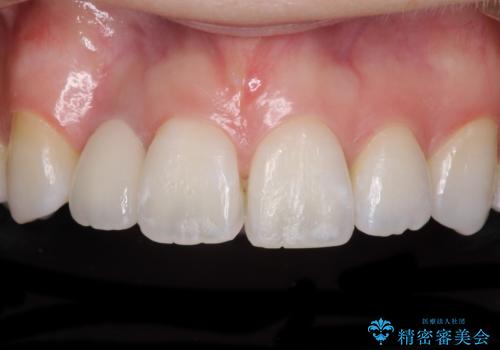

装着されていたブリッジは、支台となっている歯と欠損している歯で色が大きく異なっていましたが、オールセラミックとしたことで、全体的に色調の整った仕上がりとなりました。

歯肉ラインがきれいに整い、患者様には大変満足していただきました。